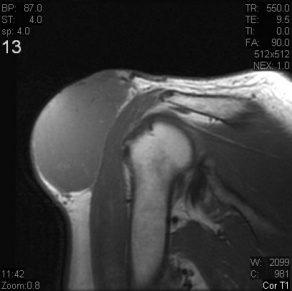

Dermatofibrosarcoma Protuberans